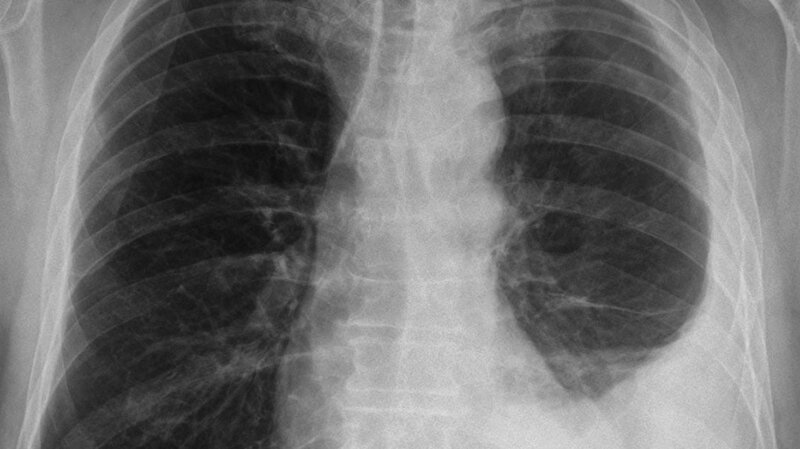

Die Therapie des Pleuramesothelioms erfordert die interdisziplinäre Zusammenarbeit von Onkologie, Chirurgie, Radioonkologie und Pneumologie. Daher ist der Patient mit Pleuramesotheliom am besten in einem Lungenkrebszentrum aufgehoben, da hier alle Fachrichtungen vertreten sind.

Schlüsselwörter: Pleuramesotheliom, Interdisziplinarität, Pleura visceralis, Pleura parietalis